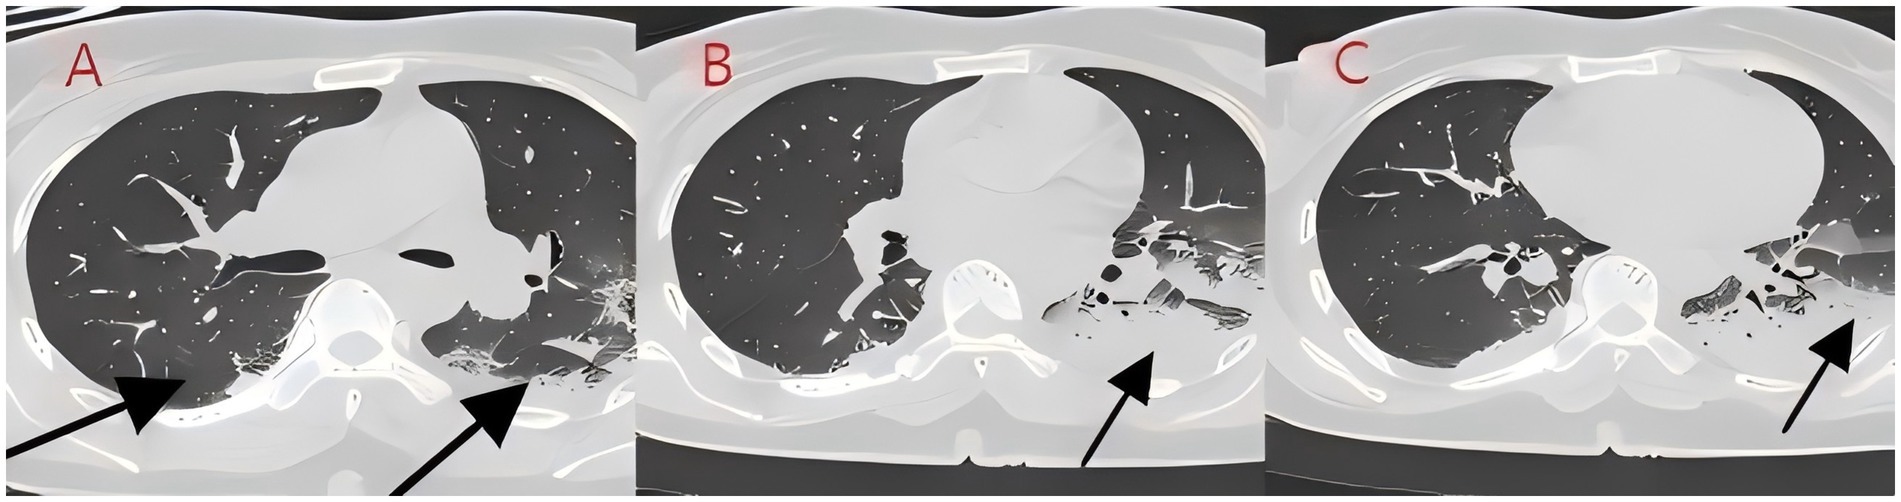

We present another case of a middle-aged Asian woman who was admitted to the hospital after drowning and inhaling a large amount of sewage. The patient inhaled stagnant wastewater from domestic sewage discharge. She showed noticeable chills and vomited a black, muddy substance while being transported. Upon admission, head, chest, and belly CT scans, along with related blood testing, were performed. Due to her critical condition, she was transferred to the ICU. Physical examination at admission revealed that her body temperature was 36.3 °C, pulse was 81 beats/min, respiration rate was 16 breaths/min, and blood pressure was 112/61 mmHg. The patient was conscious but had signs of fatigue and significant chills. Her scalp skin had a 3 × 1 cm tear. Her cardiac examination was normal; however, lung auscultation revealed bilateral wet rales, which were more pronounced in the left lung area. Furthermore, she had normal limb muscle strength and tone. There are no signs of meningeal irritation. The patient denied a history of underlying medical conditions or food or drug allergies. Emergency CT scan showed subarachnoid hemorrhage, and infectious lesions were observed in both lungs, with the left lung being primarily affected (Figure 2). The left lung also exhibits patchy, hyperdense shadows and a little pleural effusion. Moreover, her potassium levels were 2.96 mmol/L, and osmotic pressure was 288 mOsm/Kg. Similarly, the coagulation characteristics analysis revealed a D-dimer level of 3,990 μg/L. Arterial blood gas analysis showed her lactate level to be 2.50 mmol/L, pH (T) to be 7.37, pCO2 (T) to be 40.60 mmHg, and pO2 (T) to be 55.60 mmHg. Her complete blood count and C-reactive protein test results revealed that her white blood cell count was 19.77 × 109/L, whereas the C-reactive protein level was 0.51 mg/L. At admission, she was diagnosed with traumatic subarachnoid hematoma, aspiration pneumonia, type I respiratory failure, and drowning. After she was admitted to the ICU, she was given anti-infective drugs: cefoperazone–sulbactam (3.0 IV via VP every 8 h) combined with fluconazole (FLZ) injection [0.4 g via IV drip (IV gtt) once daily] to fight infection. After 2 days, the patient was re-examined due to stable vital signs, and chest CT revealed that lung infections had improved compared to the initial findings (Figure 3). After consultation with a clinical pharmacist, cefoperazone–sulbactam was changed to biapenem (0.3 g IV gtt qd every 8 h) combined with FLZ (0.4 g IV gtt qd) to remove the microorganisms. After 5 days, due to recurrent fever, she was transferred to the respiratory department and her anti-infection regimen was adjusted to oral therapy: meropenem (Mpm; 1 g IV every 8 h) combined with voriconazole tablets (400 mg every 12 h). After ruling out contraindications, tracheoscopy was performed on LB2 and LB3, with brushing and BAL of the left upper lobe. Furthermore, cytology, acid-fast stain, cell differential count, culture, and mNGS analysis of the lavage fluid were performed. Both lungs indicated improved infection lesions in the chest re-examination (Figure 4). The patient was discharged after 12 days of admission due to her inability to pay hospitalization expenses. The lavage fluid mNGS revealed the presence of T. whipplei (sequence number: 4683) and Aspergillus flavus (sequence number 9). During hospitalization, the primary medication was a dimorphic dose, but only the last dose was consistent with the mNGS report (Figure 5).

Figure 3. (A–C) Chest CT after 2 days of treatment (case 2). After bronchoscopy and antibiotic treatment for bilateral lung infections, the infection foci were absorbed significantly.